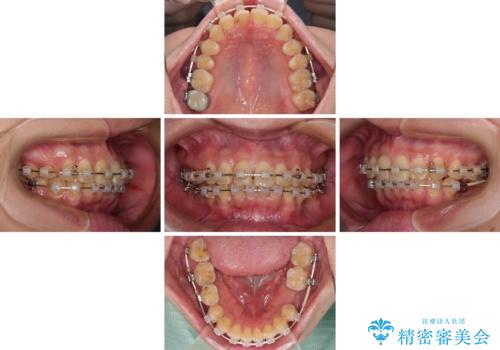

デコボコと乳歯の欠損 ワイヤー矯正とインプラント補綴治療

- 全体的なデコボコと左下乳歯部の欠損を気にして来院された患者様です。

乳歯が抜け落ちた後の後続永久歯が欠損しているため、スペースが残っておりました。

口元の突出感を気にしているのであれば欠損スペースを利用して抜歯矯正を行うことも可能ですが、横顔の印象はスッキリとしている状態であったため、矯正治療でスペースを閉じきることは不可能と判断し、インプラントによる補綴治療を行うこととしました。

第二小臼歯の欠損によるが乳歯残存や欠損が多く、この乳歯は後続永久歯に比べて幅が非常に大きいため、教聖地料によるスペースクローズが難しいことが一般的です。